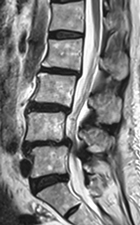

せぼね(脊椎)は7個の頚椎、12個の胸椎、5個の腰椎と仙椎から構成されます。腰椎は主に5つの骨と、間にあるクッションのような椎間板、また神経組織が通っている脊柱管から成り立っています。加齢性変化などにより腰椎の脊柱管が狭くなると、神経組織を圧迫し、下肢のしびれや痛み、脱力などを生じるようになります。この病態を腰部脊柱管狭窄症と言います。中高年における坐骨神経痛の多くは、腰部脊柱管狭窄症によるものです。高齢化とともに年々患者数が増加しており、推定患者数は約580万人と言われています。

せぼねの変形や椎間板の傷み具合、不安定性の有無、脊柱管の狭さ、またせぼね全体のバランスなどを見るためにX線検査やCT検査、MRI検査などを行います。進行例では脊柱管の狭さをより詳しく評価するために入院して脊髄造影検査や、同時にどの神経が痛みの原因となっているかを明らかにするために神経の枝に直接麻酔薬を注入する選択的神経根ブロックを行う場合があります。成人期では血管性の下肢の痛みがないか評価するために両手足の血圧を測ったり、骨粗鬆症の有無を評価するために骨密度検査を行うこともあります。